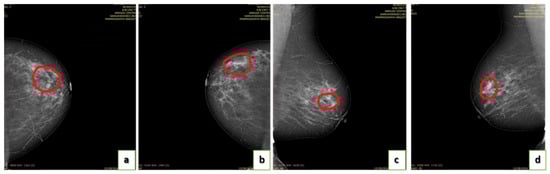

4.2. Annotation of Images

- Image labeling.

- Image validation by a committee of radiologists.